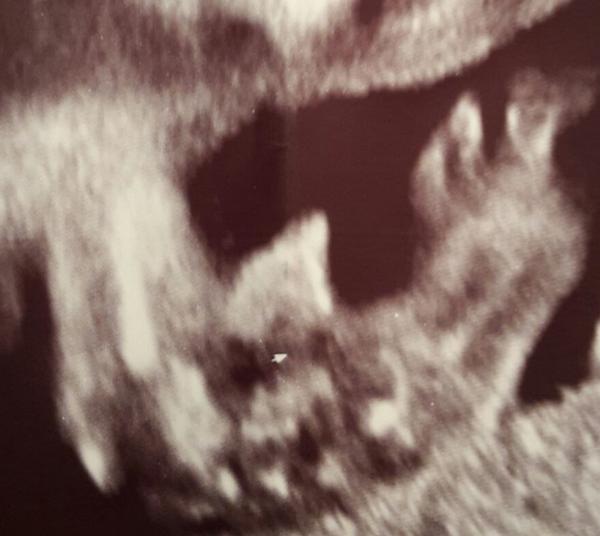

Ahojte maminky 🙂 poradite mi co vidite na fotce? V 19 tt mi lekar rekl ze tam vidi pytlik ptala jsem se tedy na kolik % rekl ze 70% no a ted jsem ve 20tt byla u jineho lekare na vetsi vysetreni a ten taky rekl ze tam vidi pindika s pytlikem a rekl ze to je 95% co tam vidite vy? Neslo lip vyfotit jelikoz bylo spatne natocene. Na leve strane je cast briska a je tam videt nozicka.

@pincola taky se ti uklidnuju🙂 ale porad mi to vrta hlavou. No je to spatny ultrazvuk.. Mimco bylo spatne natocene a manzel chtel na pamatku foto pindika 🙂 je to v levo dole. Uplne nalevo je kousicek briska pak to co vouha uprostred by mel byt pindik a vedle je nozicka. No uvidime 🙂

@taniita Já si myslím taky že je to klucik, fotku mohl zvetsit aby to tam šlo vidět pěkně tak vypadá že ho má velký ho 🙂 nám dr řekl že vidí Pytlíka a ze to je 100% kluk a pindů jsme neviděli

@taniita jasny pindik,takove mam doma dva 🙂 o par stranek zpet jsem davala porovnani utz synu a pak dcery ve 20tt,tak koukni🙂